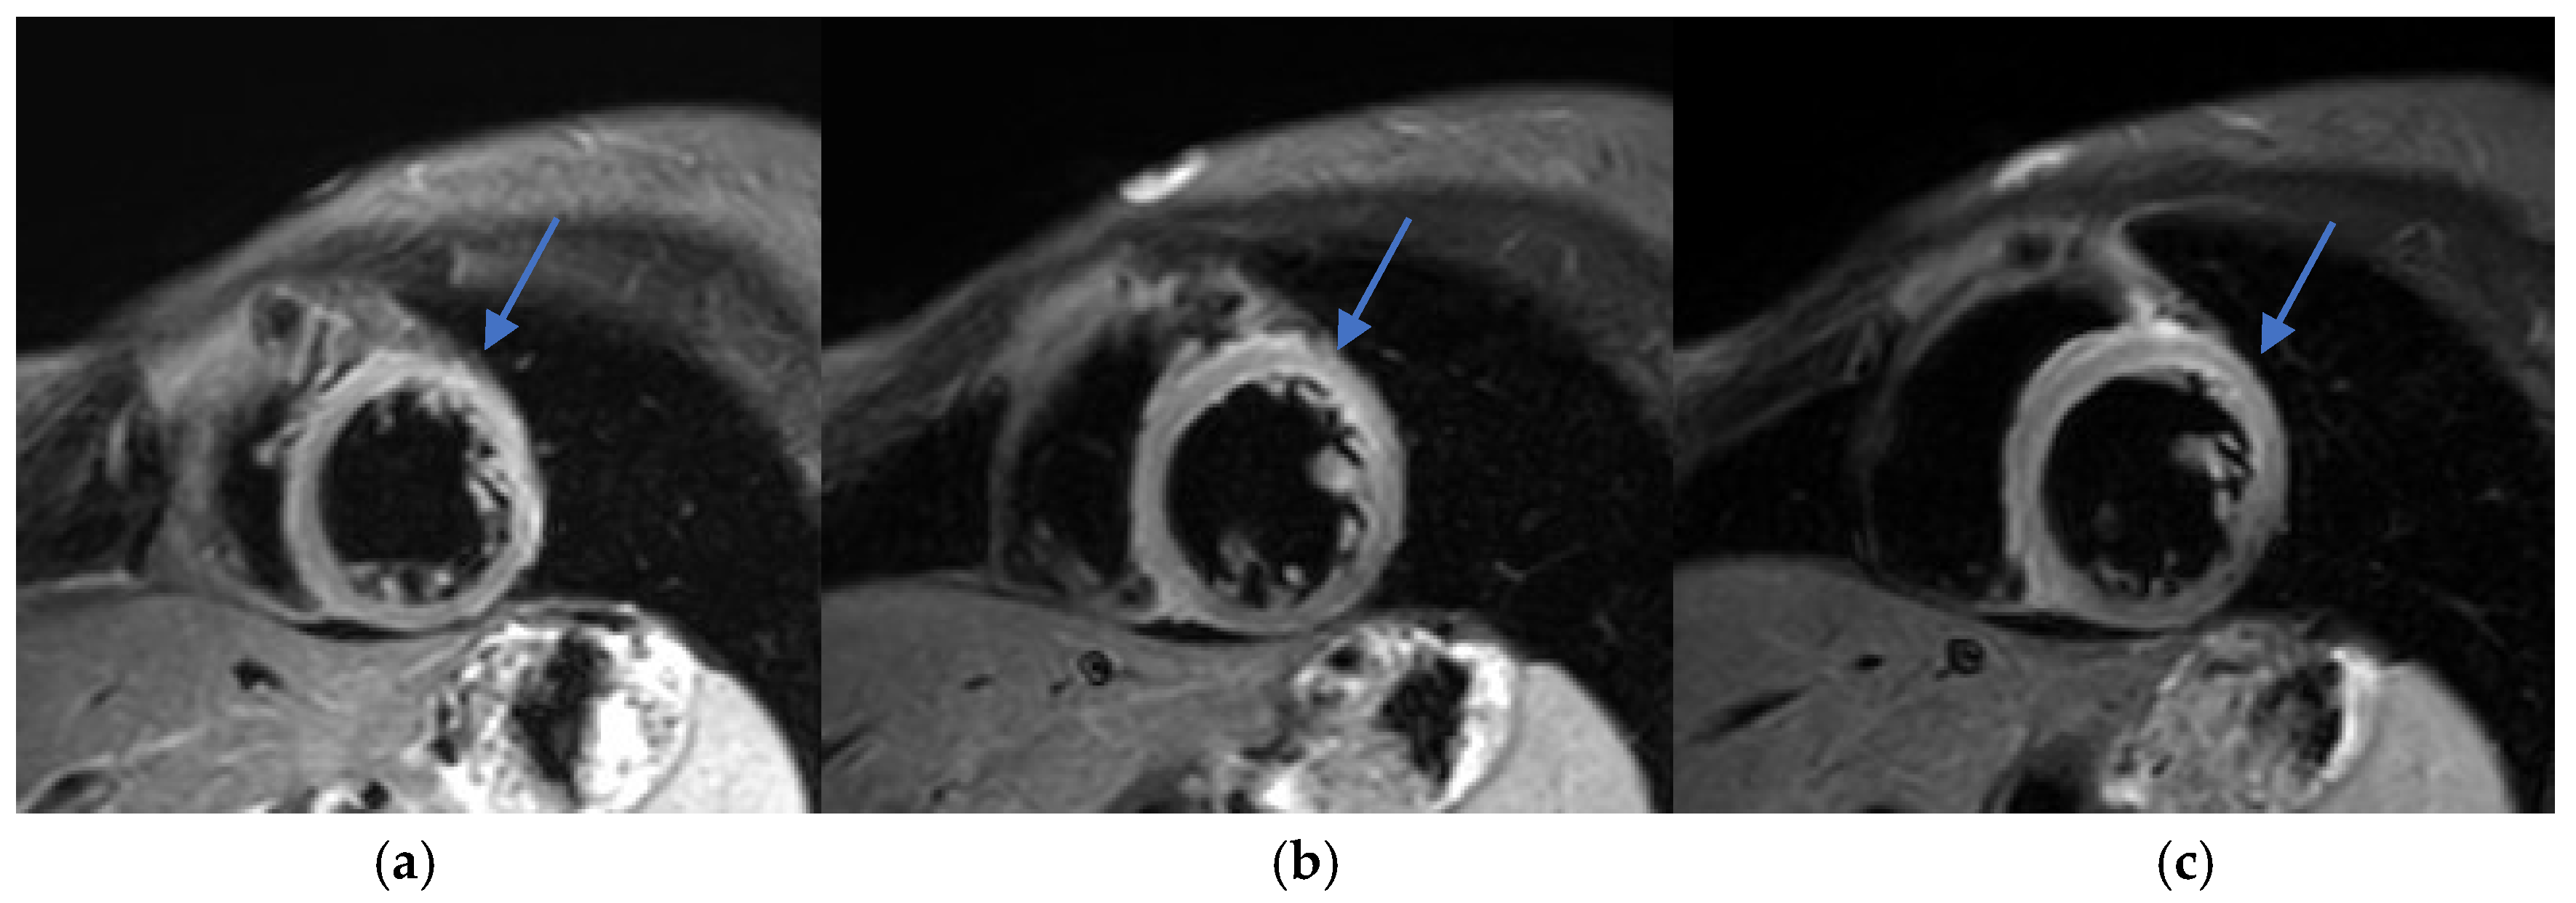

• Subepicardial LGE in the lateral wall of the left ventricle, consistent with myocardial injury.

T1 and T2 mapping sequences were not acquired, which represents a limitation in tissue characterization. Nevertheless, these findings were consistent with acute myocarditis according to the 2018 revised Lake Louise criteria (Figure 2 and Figure 3).

Early recognition and accurate diagnosis of myocarditis are critical to initiating timely management and preventing potential long-term cardiac sequelae. Diagnosing drug-induced myocarditis, especially when triggered by bisphosphonates like ZA, poses significant challenges due to nonspecific symptoms and the wide range of potential causes. In this case, CMR was pivotal, showing increased myocardial signal intensity on T2-STIR sequences (signal intensity ratio 3:1) and subepicardial late gadolinium enhancement in the lateral wall of the left ventricle (Figure 2, Figure 3 and Figure 4). These findings are consistent with acute myocarditis as defined by the 2018 revised Lake Louise criteria [22].

Figure 2. (ac) Phase-sensitive inversion recovery (PSIR) sequence, short-axis view. Subepicardial late gadolinium enhancement (LGE) is visualized in the inferior wall (arrows), consistent with myocarditis.